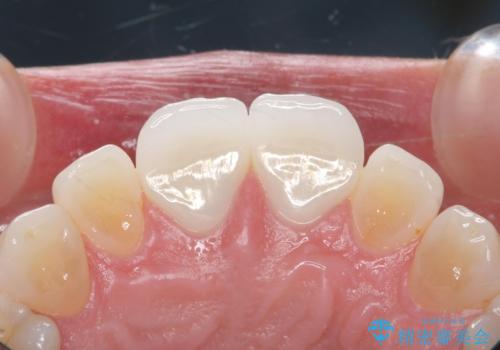

取れていない方のべニアも周囲の歯と色調が合っていなかったため、一緒にやり替えました。

脱離リスクを抑えつつ、審美性も確保できたことで大変喜んでいただけました。